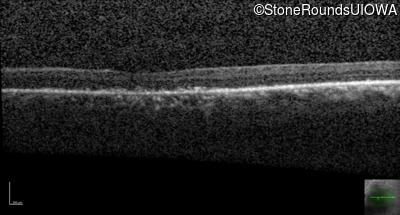

The clinical features supporting the diagnosis of Bardet Biedl syndrome in this patient include: bone-spicule-like pigmentation, narrowed arterioles and macular atrophy on ophthalmoscopy; photoreceptor loss on OCT; ulnar polydactyly, obesity, abnormal cognition, hypertension; and, normally sighted parents.